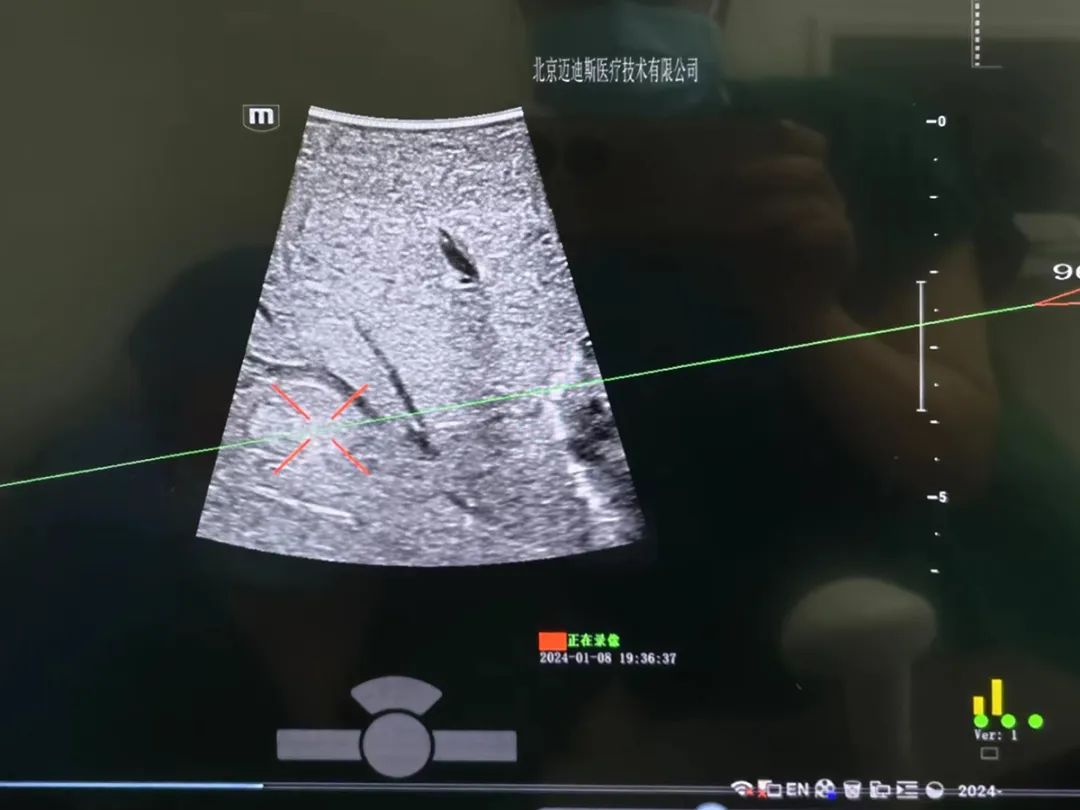

超声用电磁定位穿刺引导设备在临床医用中的模拟场景。

穿刺,是用一根同轴针穿入身体,取出肿块或积液。相比传统穿刺,超声用电磁定位穿刺引导技术不仅更具有精准性、安全性,也能减轻患者痛苦。

临床应用超声用电磁定位穿刺引导设备。